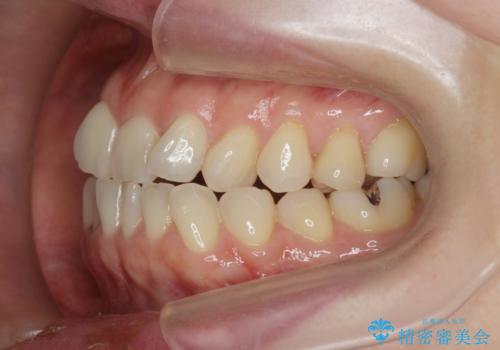

前歯の目立つガタつきをマウスピース矯正で治療

- 大きく傾いてしまった前歯のガタつきの改善を求めて来院されました。

前歯のガタつきをしっかりと取り、機能的・審美的に理想的な歯並びをマウスピース矯正で達成します。

強度のガタつきはマウスピース単体では並び切ることが難しいこともありますが、しっかりと装着していただいたことで良好な治療結果を得ることができました。